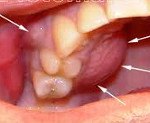

Так выглядит периостит на верхней челюсти (фото)